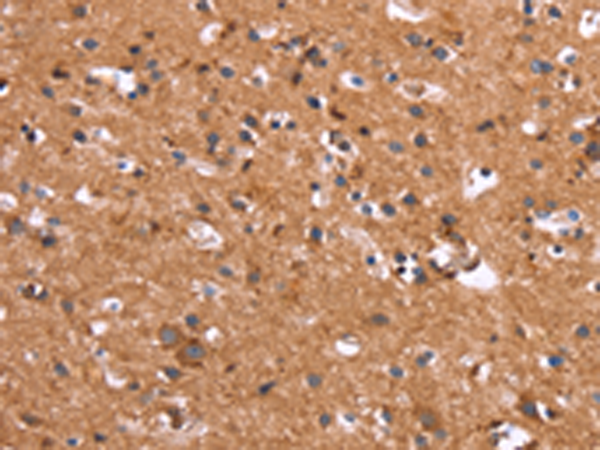

分类: 科研抗体货号: P11837别名: GIG8; ID2A; ID2H; bHLHb26应用: IHC反应种属: Human, Mouse, Rat